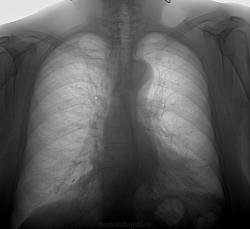

Аневризма дуги аорты?

Дебют. Может ли тень в проекции дуги аорты объяснена иначе, чем аневризма? Нужны ли в таком случае дополнительные методы исследования? Спасибо!